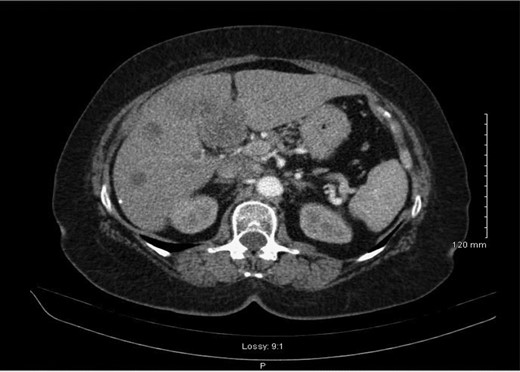

Following review of the case at a multi-disciplinary meeting, the patient was referred to oncology. A consultation was also sought from hepatobiliary which indicates that she is extremely unlikely to benefit from any liver resection as the disease has progressed far to the lung and systemic lymph nodes, however, chemotherapy and a follow-up CT were suggested. She had three cycles of chemotherapy with Cisplatin and Etoposide, and a follow-up staging CT scan demonstrated progression of the disease, predominantly in the liver with new five lesions (Fig. 3), therefore, Cisplatin and Etoposide were stopped and she was switched to second line chemotherapy in form of FOLFIRI 20% dose reduction.

Re-staging abdominal CT scan demonstrating progression of the disease.